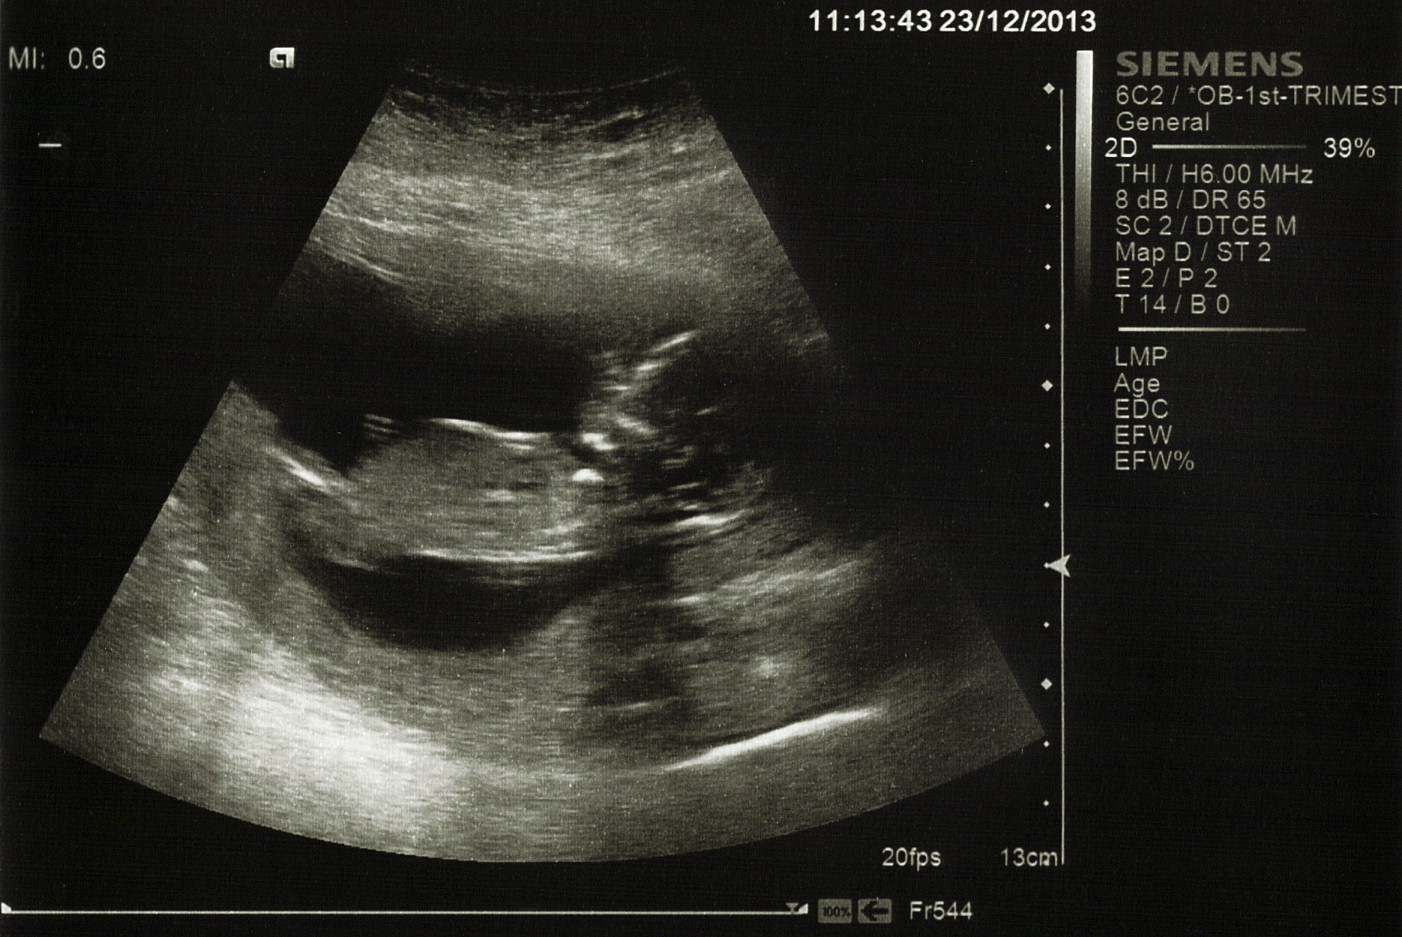

Baby has changed so much in a week, certainly the skull shape!

I couldn't see much as far as gender apart from maybe 2 small white lines on the first picture when zoomed in. Any ideas?

Attachment 15864